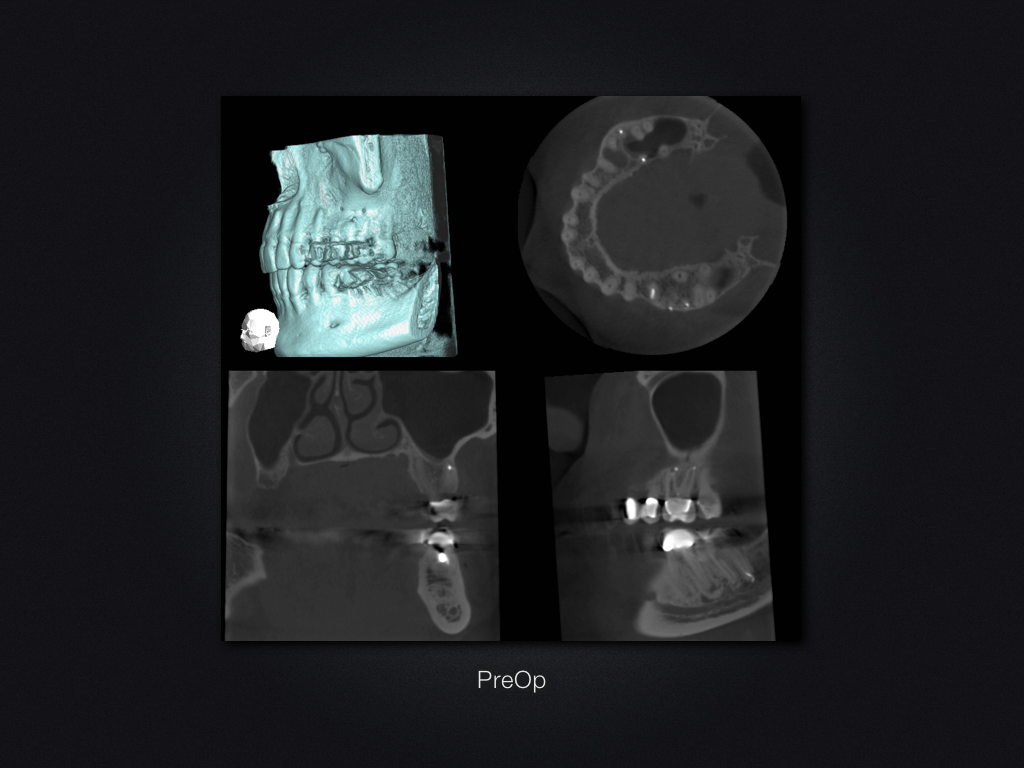

26D.005

Saving Hopeless Teeth (XXXII)